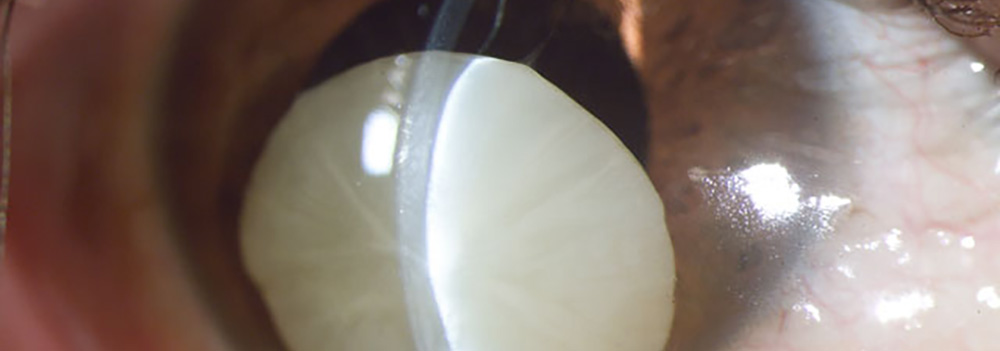

Fondo de Investigación. Francisco Barraquer Contacto Luxación de Cristalino, Catarata. Fotografía, Instituto Barraquer de América Formulario de Contacto Nombre Completo: Correo Electrónico: Comentario: Enviar